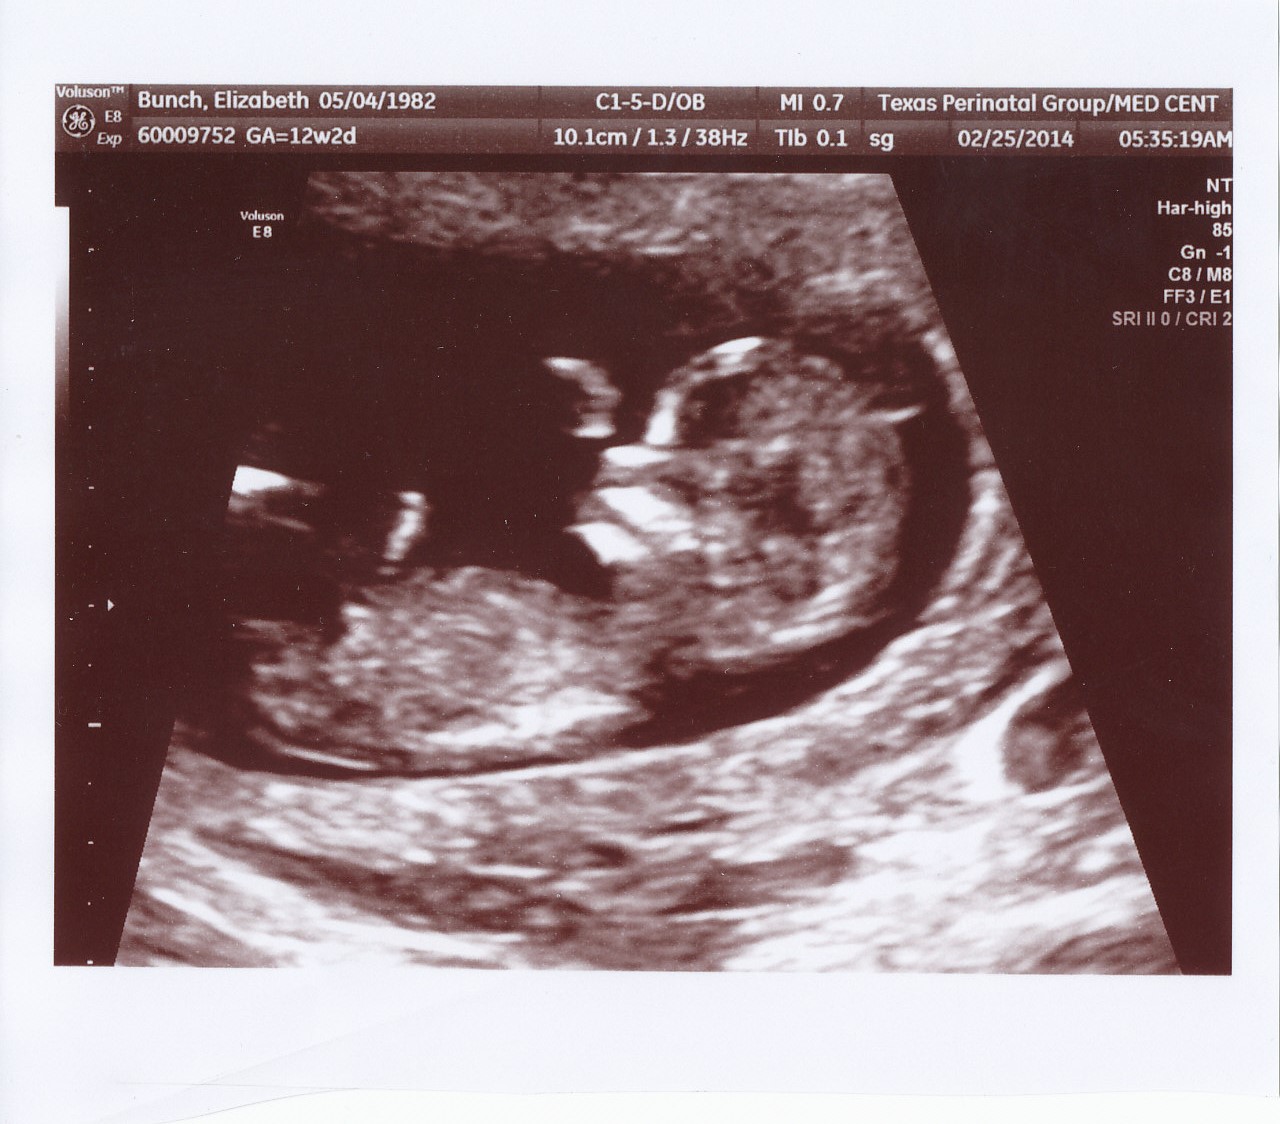

Ultrasound set for 2/17/14......TWINS! Twin A - HR 124 bpm; Twin B - HR 126 bpm

Final Ultrasound with RE 3/10/14 - Twin A - HR 176 bpm; Twin B - HR 177 bpm.